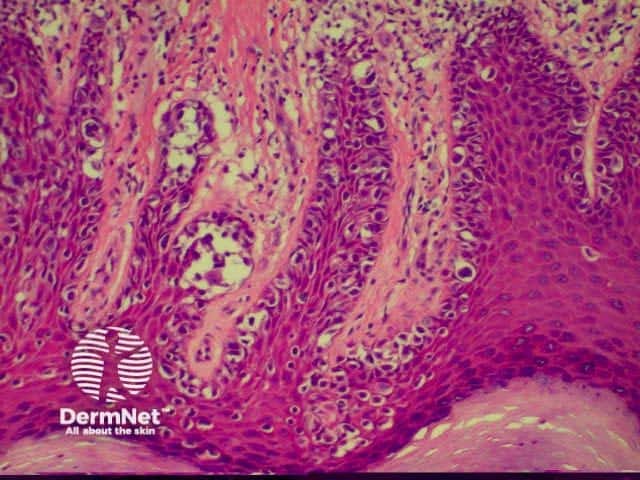

SCC is characterised by proliferation of irregular nests of abnormal squamous cells arising from the epidermis and invading the dermis. Tumours are traditionally divided into well, moderately or poorly differentiated tumours by a subjective assessment of how significantly the tumour cells differ from normal keratinocytes. In general, the greater the degree of keratinization, the better differentiated the tumour is thought to be. Except in the case of very poorly differentiated tumours, this does not have a great bearing on prognosis. More important is the depth and irregularity of invasion, particularly the presence of perineural infiltration, which is associated with a much higher rate of recurrence if not widely excised. The site of the lesion is also important; tumours of the lips and ears have a considerably higher rate of metastasis to lymph nodes.

There are several descriptive variants of SCC including spindle cell SCC and acantholytic (or adenoid or pseudoglandular SCC). These mainly are of note due to the difficulty of diagnosing the tumour as SCC, but they may also imply a slightly worse prognosis. A further rare variant is verrucous carcinoma, a lesion in which the histology has a deceptively benign appearance in that there is very little cytological abnormality. Diagnosis in these cases may be delayed and the diagnosis may not be made until several biopsies have been performed. These tumours recur locally, but do not generally metastasise.

From the above comments it can be seen that the histological features of SCCs can vary, but in general are:

Pathology of SCC Pathology of SCC Pathology of SCC Pathology of SCC